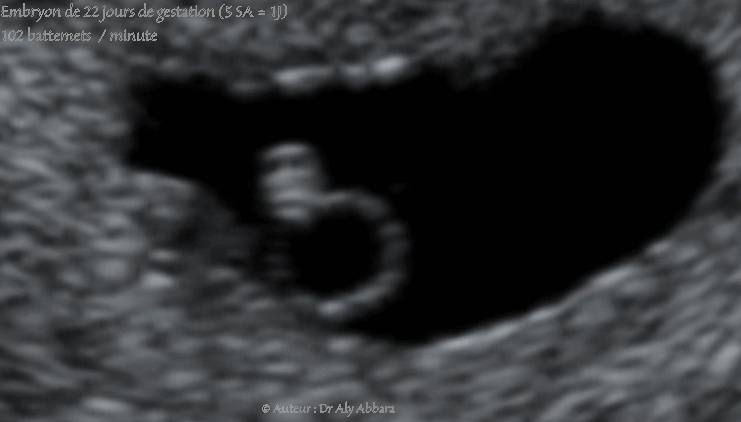

Images échographiques cardiaques montrant les premiers battements cardiaques chez un embryon âgés de 22 jours de gestation (soit cinq semaines d'aménorrhée et un jour).

La longueur crânio-caudale (LCC) = 2,45 mm

La fréquence cardiaque calculée = 102 battements/minute.

En embryologie : au cour de la 4e semaine de grossesse, le cœur commence à battre au jour 22, et le sang se met à circuler dans l'embryon au jour 24.